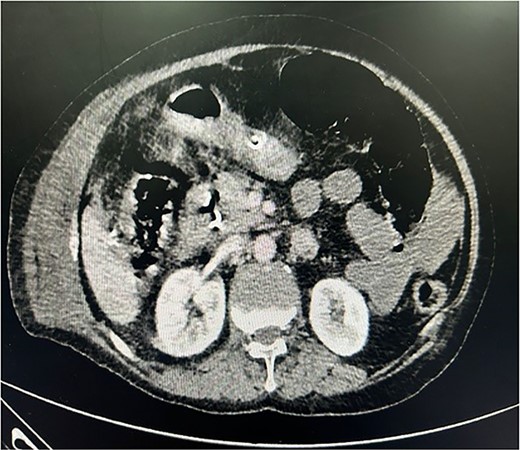

The patient was planned for surgery LC: the procedure lasted for 80 min and was performed under low flow anesthesia using sevo-flurane as the principal agent. Carbon dioxide pneumoperitoneum was maintained with intra-abdominal pressure of 12–14 mmHg. Intra-op omentum was adherent with frozen calot triangle. LC was performed without complication with the placement of abdominal drain in the sub-hepatic space. Post-operative, the patient was clinically stable, on pod-2, the patient had diffuse abdominal pain with abdominal distension, CT was done (Fig. 1) and it was s/o mild collection in anterior abdominal wall, we suspected bile leak, patient was planned for emergency laparotomy, intra op cystic duct stump leak was found and gangrenous bowel was found from mid jejunum to sigmoid colon, ileo-colic resection and end ileostomy done (Fig. 2), the remaining bowel also appears to be dusky and was not showing any signs of good vascularity. The patient condition was deteriorating after surgery and the ileostomy site showed ischaemic changes with severe sepsis and DIC, and the patient died on pod-5. Histopathological examination of the resected bowel showed features of venous infarction with patchy mucosal necrosis and oedema. No granulomas were present.

CECT whole abdomen of the patient post laparoscopic cholecystectomy